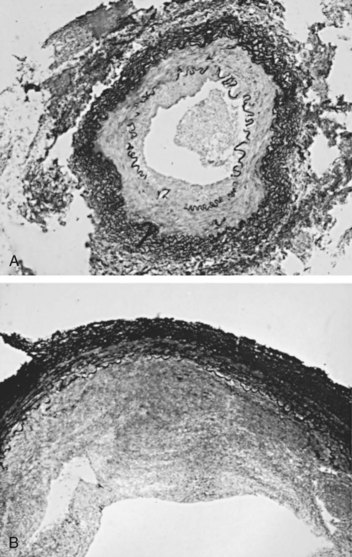

Perimedial fibroplasia occurs predominantly in young women between the ages of 15 and 30 years and has therefore been referred to, rather crudely, as girlie disease. It constitutes about 10% to 15% of the total number of fibrous lesions and occurs only in the renal artery. This is a tightly stenotic lesion that, pathologically, consists of a collar of dense collagen enveloping the renal artery for variable lengths and thicknesses. The collagen is deposited in the outer border of the media, usually replaces a considerable portion of the media, and may replace it completely in some areas (Fig. 39–5). Islands of smooth muscle are occasionally seen trapped within the collagenous ring. Special stains show that the lesion is confined within the external elastic lamina and contained in all cases by intact adventitial connective tissue. The arterial lumen may be further compromised by a process of secondary intimal fibroplasia. It has been suggested that this secondary thickening of the intima is related to slowing of blood flow through a narrowed arterial segment, with resultant platelet and fibrin deposition and subsequent fibrous organization.

Figure 39–5 Cross section of the main renal artery in a girl with perimedial fibroplasia demonstrates a dense collagenous collar (arrows) involving the outer media of the vessel, which causes a severe progressive stenosis.

(From Novick AC. Renal vascular hypertension in children. In: Kelalis PP, King LR, Belman AB, editors. Clinical pediatric urology. Philadelphia: WB Saunders; 1984.)